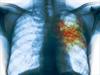

У взрослых основной метод выявления

туберкулеза – ФЛЮОРОГРАФИЯ.

Туберкулёз лёгких может длительное время протекать бессимптомно или малосимптомно и

обнаружиться случайно при проведении флюорографии или на рентгеновском снимке грудной клетки,

может быть также обнаружен при постановке туберкулиновых проб (проба Манту, Диаскинтест).